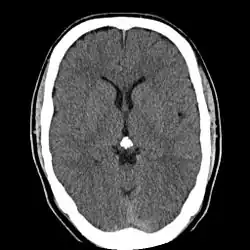

Calcificación

La glándula pineal es a menudo visible en las imágenes tomográficas (TAC y RM) cuando está calcificada. La calcificación de la glándula pineal es común en los adultos, pero también se ha observado en niños a partir de los 2 años de edad. Las tasas de calcificación varían ampliamente según el país y su frecuencia aumenta con la edad. La calcificación de la pineal está asociada con los cuerpos arenáceos ("acérvulos" o "arena cerebral").[21] [22]